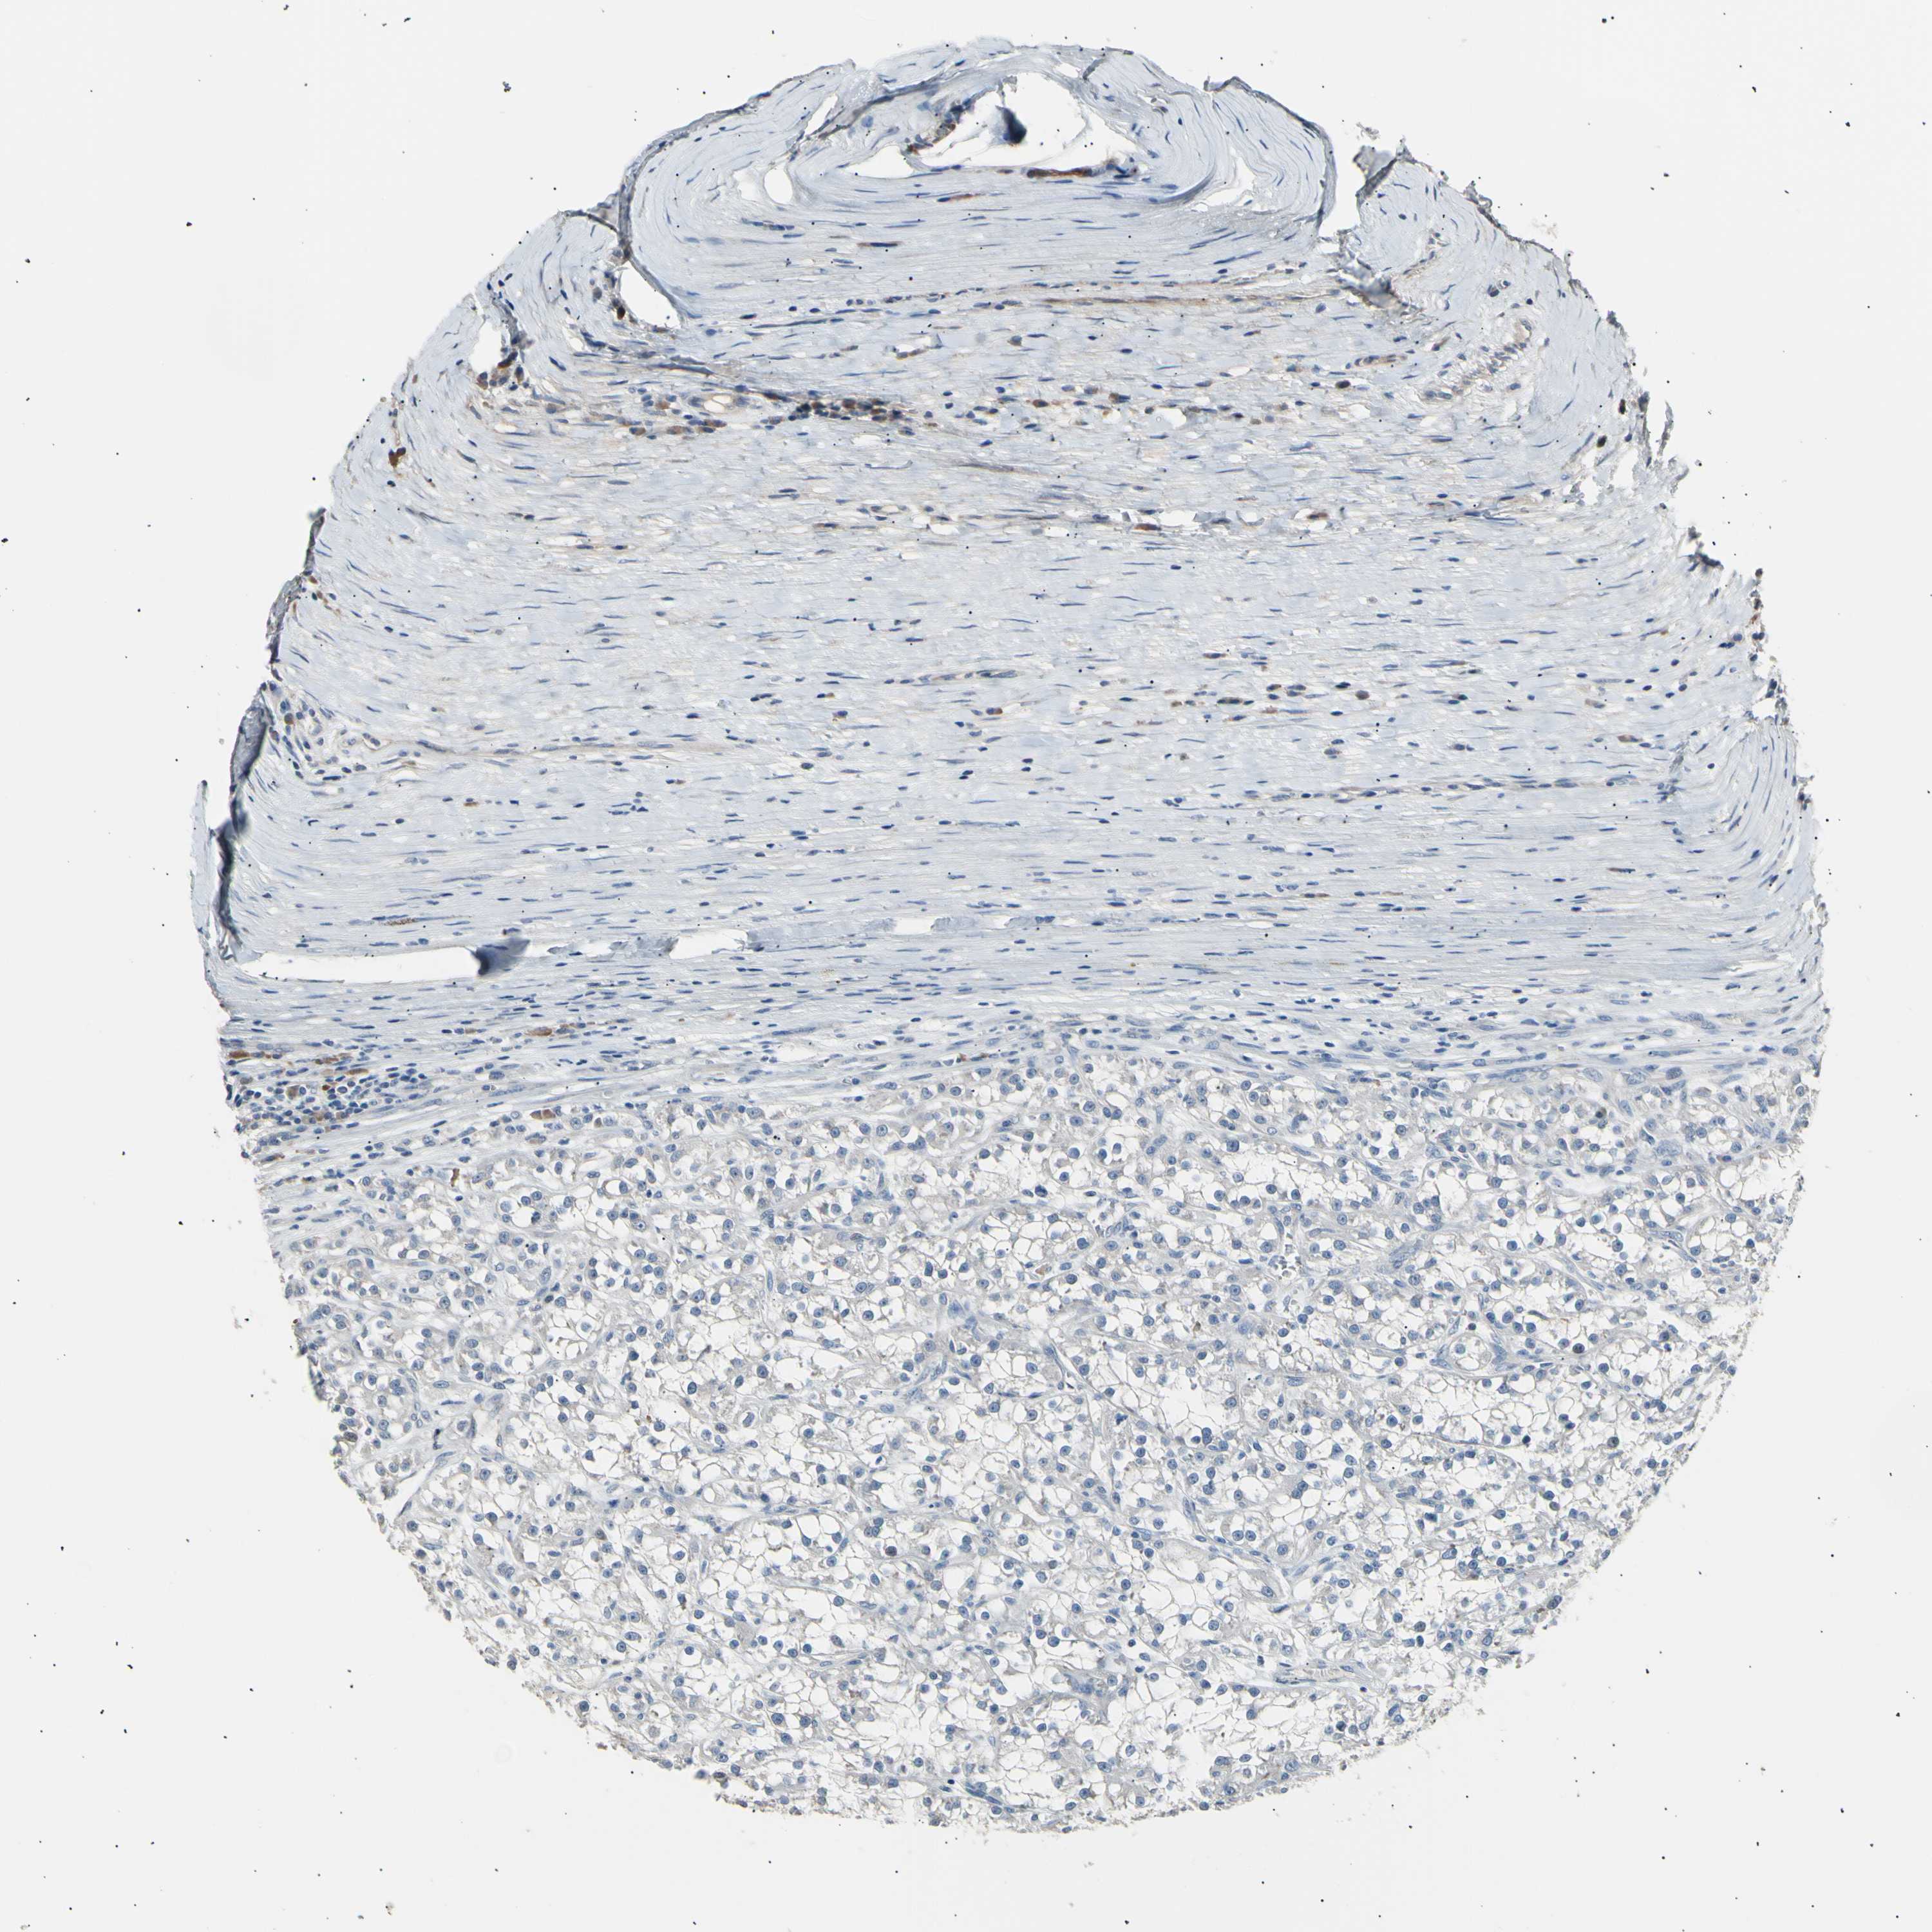

KIDNEY RENAL CLEAR CELL CARCINOMA (VALIDATION) - Interactive survival scatter ploti

The Survival Scatter plot shows the clinical status (i.e. dead or alive) for all individuals in the patient cohort, based on the same data that underlies the corresponding Kaplan-Meier plots. Patients that are alive at last time for follow-up are shown in blue and patients who have died during the study are shown in red.

The x-axis shows the expression levels (FPKM) of the investigated gene in the tumor tissue at the time of diagnosis. The y-axis shows the follow-up time after diagnosis (years). Both axes are complimented with kernel density curves demonstrating the data density over the axes. The top density plot shows the expression levels (FPKM) distribution among dead (red) and alive patients (blue). The right density plot shows the data density of the survived years of dead patients with high and low expression levels respectively, stratified using the cutoff indicated by the vertical dashed line through the Survival Scatter plot. This cutoff is automatically defined based on the FPKM cutoff that minimizes the p-score. The cutoff can be changed by dragging the vertical line or by entering a cutoff value in the square labeled "Current cut-off".

Under the Survival Scatter plot the p-score landscape (black curve; left axis) is shown together with dead median separation (red curve; right axis). Dead median separation is the difference in median mRNA expression between patients who have died with high and low expression, respectively. It is calculated as follows: median FPKM expression of dead patients with high expression - median FPKM expression of dead patients with low expression. This is intended to aid the user in visually exploring custom cutoffs and the associated p-scores and dead median separation.

Individual patient data is displayed and can be filtered by clicking on one or more of the category buttons on the top of the page. Categories describing expression level and patient information include: high, low, alive, dead, female, male and tumor stages. The scale of the x-axis can be toggled between linear and log-scale by clicking on the "x log" button. Mouse-over function shows TCGA ID, patient information and mRNA expression (FPKM) for each patient.

& Survival analysisi

Kaplan-Meier plots summarize results from analysis of correlation between mRNA expression level and patient survival. Patients were divided based on level of expression into one of the two groups "low" (under cut off) or "high" (over cut off). X-axis shows time for survival (years) and y-axis shows the probability of survival, where 1.0 corresponds to 100 percent.

LDLR is not prognostic in Kidney Renal Clear Cell Carcinoma (validation)

Best expression cut offi

Based on the FPKM value of each gene, patients were classified into two groups and association between prognosis (survival) and gene expression (FPKM) was examined. The best expression cut-off refers the FPKM value that yields maximal difference with regard to survival between the two groups at the lowest log-rank P-value. Best expression cut-off was selected based on survival analysis .

When clicking on this number, the vertical dashed line indicating cut-off, the interactive survival plot, and the Kaplan-Meier curve will be adjusted to show results based on the best expression cut-off.

: 5.41

TCGA RNA samplesi

RNA-seq data is reported as average FPKM (number Fragments Per Kilobase of exon per Million reads), generated by the The Cancer Genome Atlas (TCGA) .

Normal distribution across the dataset is visualized with box plots, shown as median and 25th and 75th percentiles. Points are displayed as outliers if they are above or below 1.5 times the interquartile range. FPKM values of the individual samples are presented next to the box plot.

Average pTPM 4.0

Number of samples 100